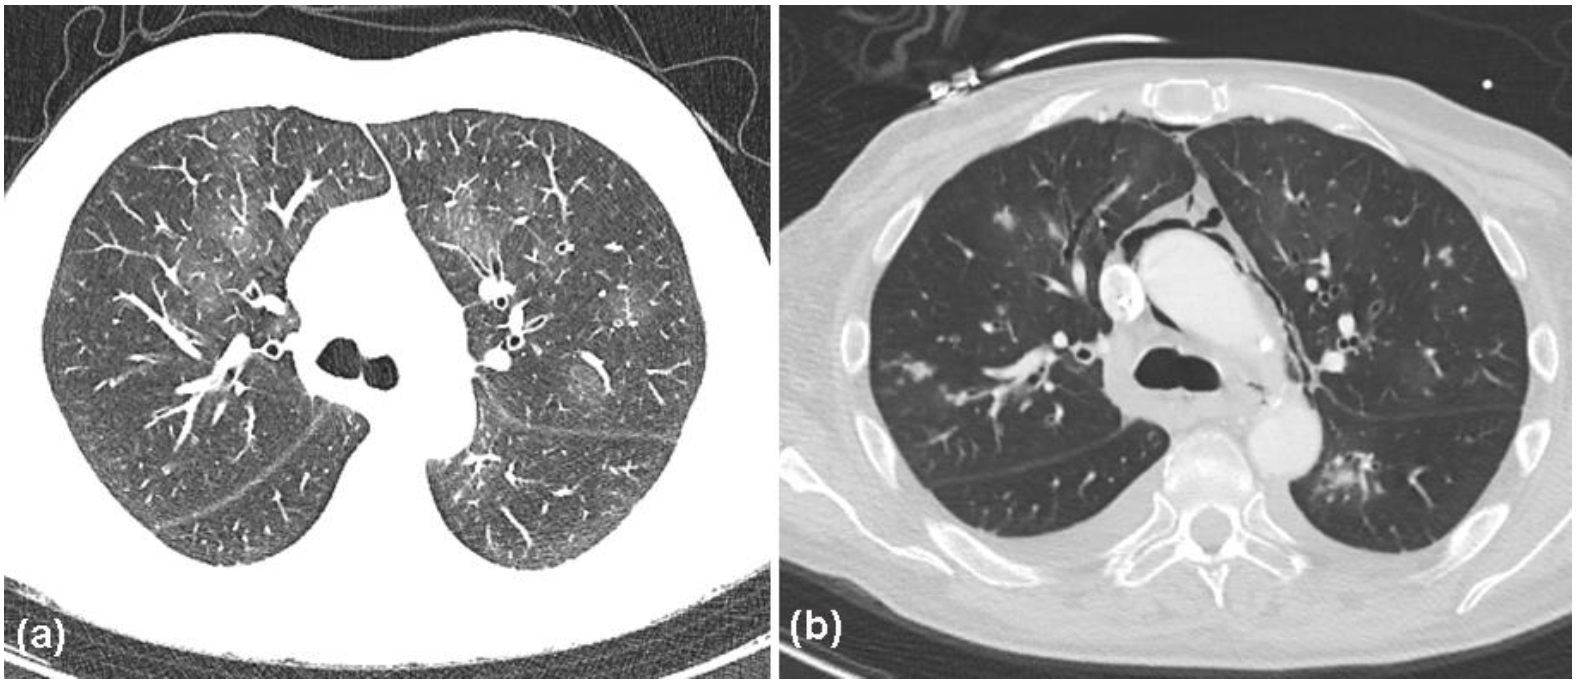

Figure 7.

Computed tomography (CT) scans of the chest. (a) Subtle mosaic attenuation, ground-glass opacities, bronchiectases, and bronchial wall thickening, consistent with a diagnosis of bronchiolitis obliterans (BO); (b) pneumomediastinum as a further complication of BO.

However, several blood cultures remained negative. Moreover, the patient developed spontaneous subcutaneous emphysema and pneumomediastinum, associated with the Macklin effect. Importantly, bronchoscopy, gastroscopy, and thoracic CT and angio-CT did not reveal evidence of perforation or trauma. Combined treatment with meropenem, linezolid, ganciclovir, and voriconazol was initiated. Nevertheless, the patient’s condition worsened and he finally succumbed to respiratory failure after a 1-week period. An autopsy was refused by the relatives of the patient.

In the present case, it remains obscure whether humoral autoimmunity played a role at the beginning of the disease, since this was never determined. As would be expected, after the employment of anti-CD20 therapy, humoral autoimmune phenomena, i.e., circulating or deposited antibodies, were not detected. Interestingly, there are several reports on PAMS patients without detectable autoantibodies (e.g., desmoglein 1/3, envoplakin, and BP-230) [9,25,26,27,28]. Interestingly, most of these were patients who had received prior treatment with anti-CD20 antibodies for their lymphoproliferative disorder before the development of PAMS [25,26,27,28]. These observations strongly support the importance of autoreactive T-cell responses in PAMS. Interestingly, the frequency of PAMS diagnoses has declined, most likely due to the increased use of CD20-directed antibodies, which lead to negative results in direct and indirect immunofluorescence assays. A correct diagnosis is further complicated by the fact that PAMS, with its T-cell-mediated lichenoid phenotype, may mimic erythema multiforme, SJS, TEN, and graft-versus-host disease. Nonetheless, Lim et al. recently reported a patient with autoantibody-negative lichenoid PAMS, with no preceding anti-CD20 therapy, indicating that cell-mediated immune responses may predominate in some patients with PAMS [9]. Nevertheless, anti-CD20 therapy for the treatment of lymphomas, as well as immunosuppressive therapy for PAMS, carry a high risk for complications, due to infections. In the present case, endoscopic investigations showed severe sloughing of the esophageal epithelium. Furthermore, bronchoscopy revealed erythematous, highly vulnerable airway mucosa. Notably, the patient also developed spontaneous pneumomediastinum, associated with the Macklin effect, which can represent a complication of bronchiolitis obliterans [29,30,31]. Although generally occurring secondary to trauma, pneumomediastinum can also develop due to underlying lung conditions, such as asthma and bronchiolitis obliterans [29,30,31]. The Macklin effect can be frequently demonstrated in patients with spontaneous pneumomediastinum of non-traumatic respiratory causes, by multidetector-row CT. Hence, Sakai et al. [31] suggested that the Macklin effect, as revealed by CT scans, may be useful in differentiating respiratory from other causes of pneumomediastinum [31]. Accordingly, in this case, bronchoscopy, gastroscopy, and thoracic CTs did not reveal evidence of perforation or other trauma. Similar to another case of PAMS, reported by Odanit et al. [32], the patient discussed here very likely succumbed to his complicated bronchiolitis obliterans associated with co-infection by several pathogens.